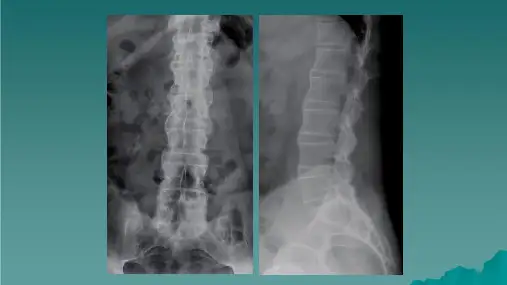

强直性脊柱炎(Ankylosing Spondylitis,AS)是一种慢性、进行性的关节炎,

主要累及脊椎及骨盆关节,常表现为脊柱强直及关节疼痛。